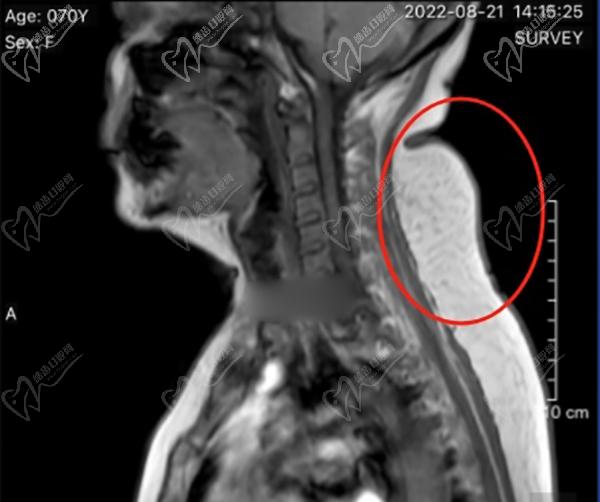

韋元強(qiáng)醫(yī)生做富貴包的價(jià)格在3萬元左右。他的富貴包手術(shù)包括吸脂和微創(chuàng)技術(shù)兩種方法。吸脂的價(jià)格在2.2萬元左右,而微創(chuàng)技術(shù)的價(jià)格在3萬元以上。這些價(jià)格包括了手術(shù)費(fèi)用、麻醉費(fèi)用、住院費(fèi)用和護(hù)理費(fèi)用。韋元強(qiáng)醫(yī)生的富貴包技術(shù)非常可靠,他會(huì)根據(jù)每個(gè)患者的身體狀況和美學(xué)需求來個(gè)性化設(shè)計(jì)手術(shù)計(jì)劃。

韋元強(qiáng)乳化抽吸術(shù)消除富貴包徹低,難反彈。

很多嘗試過針灸、按摩、拔罐、艾灸的朋友,當(dāng)時(shí)有點(diǎn)成效,但是沒多久就感覺富貴包變得更大了。韋元強(qiáng)醫(yī)生做的乳化抽吸術(shù)消除富貴包手術(shù),是微創(chuàng)局麻手術(shù),通過乳化的方式將發(fā)硬的脂肪乳化后,再吸出體內(nèi),比較徹 底,術(shù)后很難反彈。整個(gè)手術(shù)過程需要2.5個(gè)小時(shí)左右,手術(shù)僅有1個(gè)針眼大的創(chuàng)口,就在富貴包下面5cm的地方,比較隱蔽,剛做完手術(shù)后會(huì)感覺肩頸放松了很多,后頸部的鼓包也消失了,術(shù)后觀察一段時(shí)間沒有問題就可以出院了。術(shù)后修復(fù)期穿塑身衣加壓消腫就好了。